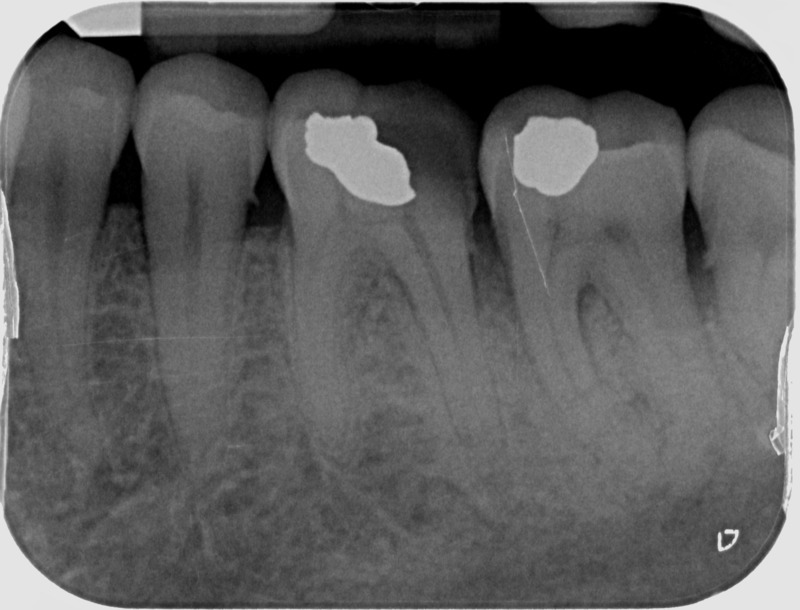

Avant

• Apexification : Chez le jeune enfant, une dent immature victime d’un traumatisme ou d’une carie volumineuse peut poser problème. Si la pulpe agressée se nécrose, alors la racine ne s’édifie plus et une lésion inflammatoire se développe au niveau osseux. L’apexification, par apposition d’un matériau biocompatible dans la racine, cherche à induire la formation d’une barrière artificielle à l’extrémité de celle-ci, et permettre la cicatrisation de la lésion dans le but de maintenir la dent en bouche à long terme.